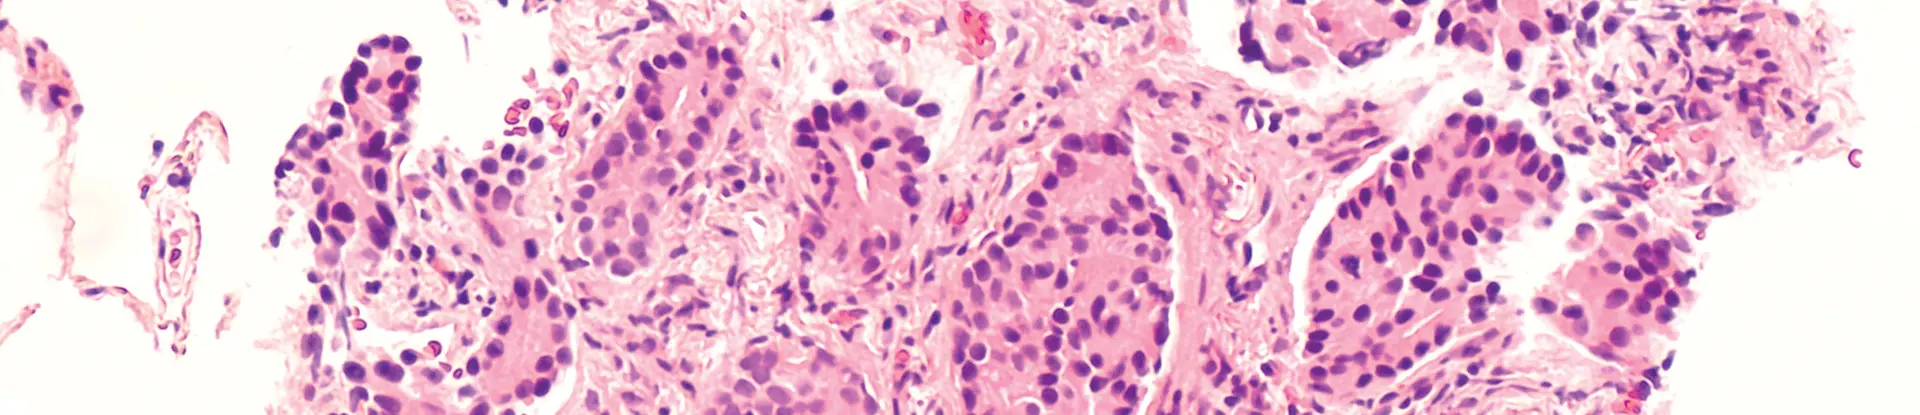

stained pathology slide with irregular blood cells indicating lymphoma.

SwRI created an AI tool that analyzes stained pathology slides, looking for irregular blood cells that indicate lymphoma.